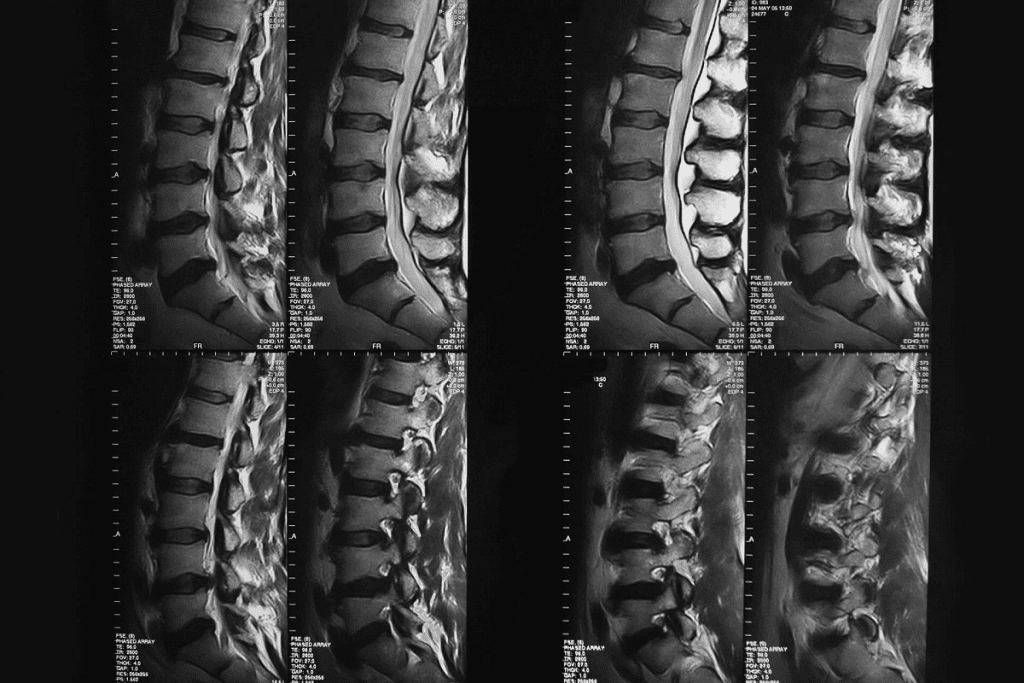

Bone scintigraphy uses radioactive isotopes to show what’s happening in our bones. It’s key for spotting and tracking bone problems.

How Radioactive Isotopes Help Visualize Bone Activity

Radioactive isotopes, or radionuclides, help see bone activity in bone scintigraphy. Injected into the body, they go to active bone areas, like diseased or injured spots. Technetium-99m methylene diphosphonate (Tc-99m MDP) is the top choice because it sticks to bone well.

Tc-99m MDP helps find bone issues like cancer, fractures, and infections. It shows where bone activity is off, helping doctors see how bad the disease is and if treatments are working.

The Role of Gamma Rays in Bone Imaging

Gamma rays from the isotopes are caught by a gamma camera. These rays are like X-rays but with different strengths. The camera makes images of the skeleton, showing bone activity.

Gamma cameras are super sensitive to these rays. This lets them spot tiny changes in bone activity. It makes bone scintigraphy great for catching and tracking bone diseases early.

How Bone Scintigraphy Machines Work

Bone scintigraphy machines, or gamma cameras, catch gamma rays from the isotopes in bones. They move around the patient, taking pictures from different sides. Then, they make detailed bone images, showing where things are off.